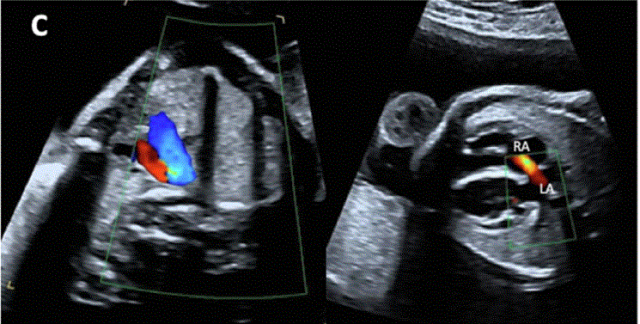

图27进展性主动脉狭窄。一例23周胎儿的严重主动脉狭窄,伴有扩张和低动力性左心室(LV)伴心内膜弹性纤维变性。(A) 彩色多普勒显示,主动脉瓣(箭头)开始出现花彩血流(左),频谱多普勒显示阶差为 25 毫米汞柱(右(B) 二尖瓣(MV)流入是单相的,持续时间短(左),二尖瓣反流提示左心室收缩压高(46毫米汞柱压力梯度加左心房压力;右图)。(C)存在逆行主动脉弓流(红色,左)和左至右心房流(红色、右)是预测由于通过左心的流量减少而在妊娠期间发展的进行性左心发育不全的额外发现。(D)LV逐渐变为球状,长度缩短,到36周时不再形成心尖。

图29胎儿Ebstein异常和TV发育不良。(A)在该胎儿中,严重的三尖瓣反流与进行性心脏增大有关,尤其是右心房(RA)扩张,如这些在19周和34周时的系列图像所示,并且可能与心力衰竭/水肿的演变有关。(B-D)四腔切面中胎儿严重Ebstein异常显示严重心脏扩大的图像。(C)从矢状切面可见广泛的三尖瓣反流(箭头),由于室间隔瓣叶移位,反流起源于TV瓣环下方,甚至向 RV 流出道射流。彩色多普勒和 CW 多普勒显示也有连续的肺动脉反流。(D) 后一项发现表明,右心室无法产生足够的压力来打开肺动脉瓣